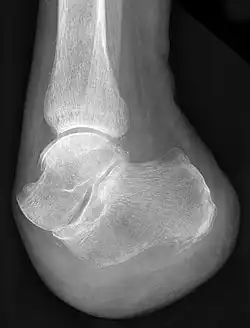

Radiographie du pied après amputation selon Chopart.

François Chopart est notamment connu pour avoir mis au point une technique d'amputation, longtemps appliquée sur les champs de bataille, consistant à sectionner le pied non pas à travers l'os, mais en suivant les articulations talo-naviculaire et calcanéo-cuboïdienne (qui ont d'ailleurs été regroupées sous la dénomination d'articulation de Chopart en hommage au chirurgien).